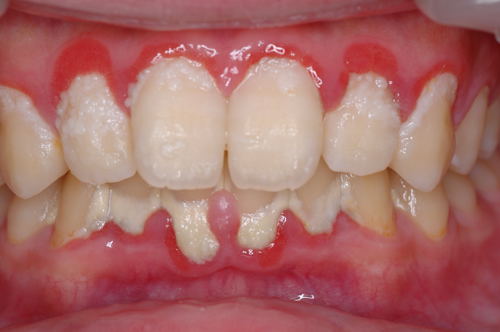

| これは重度の歯肉炎です。原因は多量の歯垢。ほとんど歯磨きをしていないと思われます。歯垢に触れている歯肉が赤くなっているのが分かりますか?炎症が起きており、少し触っただけで血膿が出、口臭もひどいです。歯肉がだいぶ弱っていますので、一番軟かい歯ブラシを使って歯垢を取ってください。歯肉のマッサージも少しずつやらないと健康な硬い歯肉には戻りません。 頑張ってください。 |